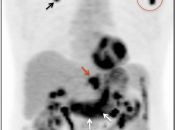

The difficulty with PET/CT imaging and gastric cancer is that it is both easy to overlook and easy to over-call.

Normal FDG uptake involving the stomach can be extremely variable. It is not uncommon to see diffuse intense uptake throughout the entire stomach or intense uptake limited to only a segment of the stomach (fundus, body or antrum).

In general, we raise a suspicion of gastric malignancy if:

• Focal or regional hypermetabolic activity is accompanied by at least the suggestion of associated wall thickening (often difficult to assess if the patient’s stomach is suboptimally distended with water or oral contrast);

• Uptake is extremely focal (more likely to represent malignancy or ulcer);

• Focal/segmental uptake is extremely intense.

• Obviously, signs of associated metastatic disease on the scan give the radiologist much greater confidence in reporting a suspected primary gastric lesion.